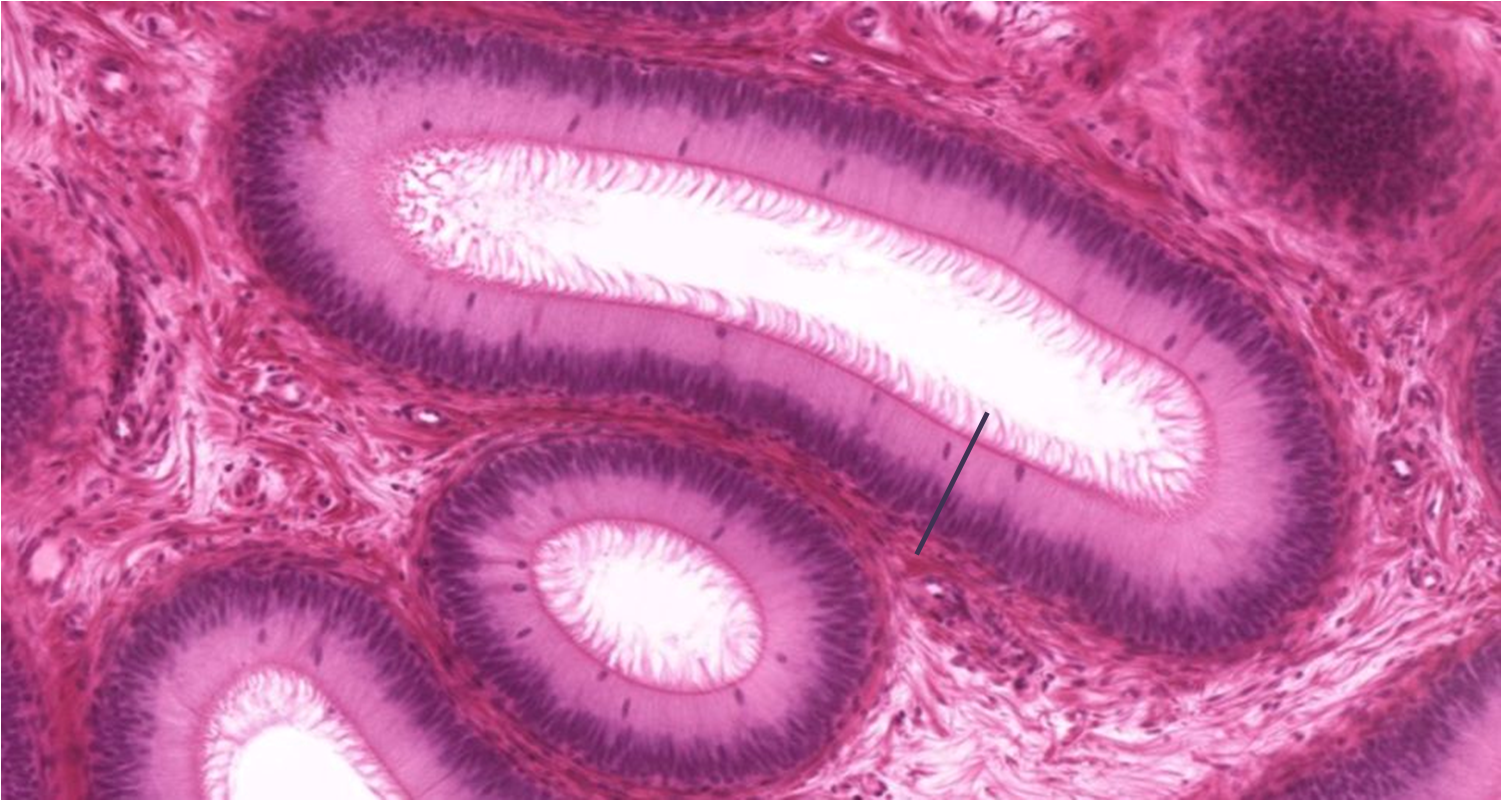

Trompa uterina

1: Trompa uterina - mucosa

2: Camada muscular - músculo liso